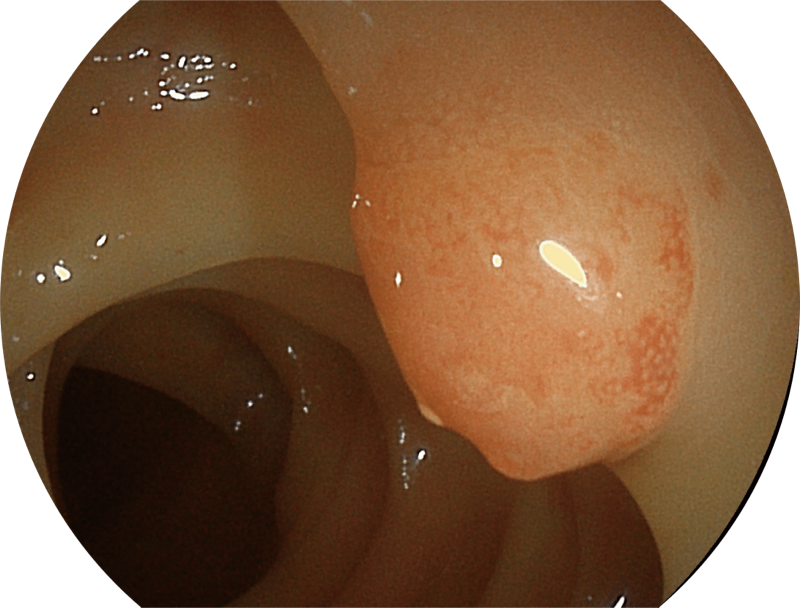

百万级像素高清传感器,1080P全高清视频信号输出,图像清晰。

弯曲角度大,方便观察食管下段贲门、胃底部等难以观察到的部位,减少盲区。